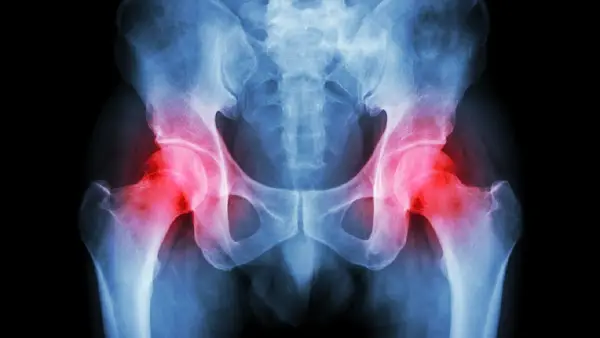

在骨科手术中,麻醉方式的选择对手术的成功和患者的恢复至关重要。以股骨头坏死为例,这类手术通常需要较长时间的麻醉支持,且术后疼痛管理复杂。本文将探讨全麻与神经阻滞在股骨头坏死手术中的应用及其优势。

在股骨头坏死手术中,全麻与神经阻滞的结合使用,不仅能够提供良好的手术条件,还能有效控制术后疼痛,加速患者的康复进程。本文将详细解析这两种麻醉方式的应用及其在股骨头坏死手术中的具体优势。